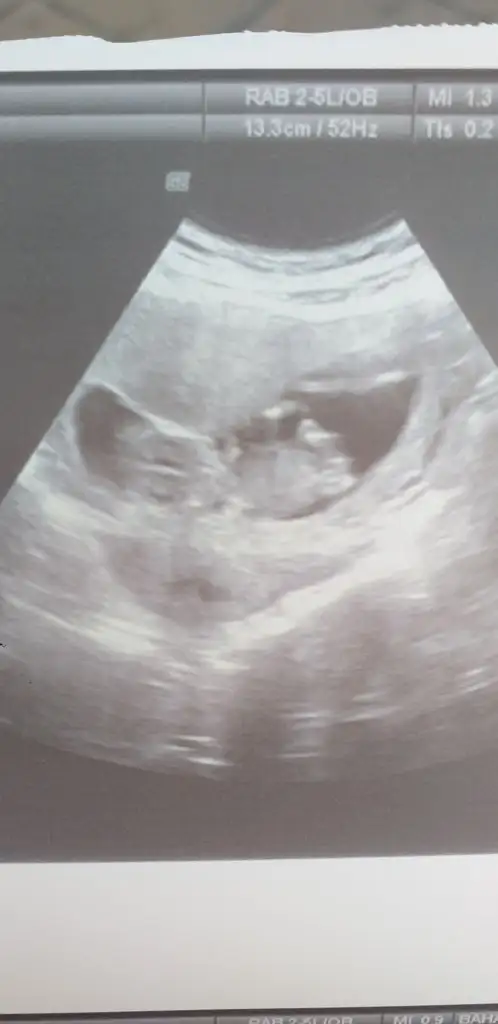

13 haftalik burada 16 da gelin dedi doktorum. bakalim tesekkur ederim cok cokKaç haftalık sanki kız gibi ama 11+ yada 12+ olmalı usg buyuk görünüyor gibi 13+ sonrası organ tamamlanmış oluyortam emin değilim tahminimden kız gibi gibi diyorum

İlk usgdeki nubu tam dik degil yakınlaştırınca bozuluyor foto digerleri net değil başka varsa tahmin ederim tam dik degil paralelde değil kafa yapısınıda ekledim kızda karar verdim aslında kızda olmayada bilir

Ayyy cok merakliyim bilmiyorumİlk usgdeki nubu tam dik degil yakınlaştırınca bozuluyor foto digerleri net değil başka varsa tahmin ederim tam dik degil paralelde değil kafa yapısınıda ekledim kızda karar verdim aslında kızda olmayada bilirgenelde kafa şeklide tutmuyor